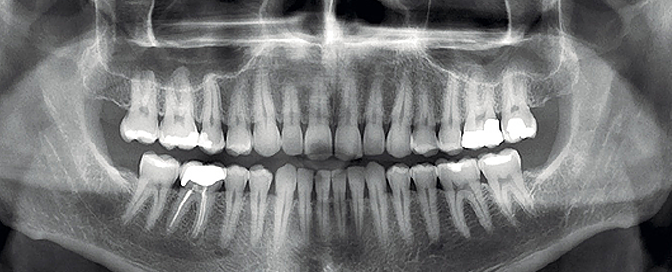

Panoramska radiografija, ortopantomografija, ortopantomogram ili najkraće i najčešće „ortopan“ je dijagnostički osnovna i najvažnija snimka u stomatologiji koja se najčešće izrađuje kao orijentacijska snimka pri prvom pregledu.

Snimka omogućuje dvodimenzionalni prikaz veliko anatomske regije, te ima vrlo široku uporabnu vrijednost u svim područjima stomatologije. Odlična je za postavljanje pravilne dijagnoze, planiranja terapijskih stomatoloških postupaka te praćenja razvoja bolesti i rezultata stomatološkog liječenja.

Što sve možemo vidjeti na ortopanu?

Ortopan zuba omogućuje uvid u više važnih struktura koje su nam bitne u stomatologiji. Istovremeno se ortopanom vidi gornja i donja čeljust, sve koštane strukture, svi zubi, maksilarni sinusi i temporomandibularni zglob koji je važan za pravilno funkcioniranje mišića lica.

Na snimci možemo vrlo dobro uočiti traumatske promjene, opsežne karijesne lezije, parodontne i periapikalne patološke procese, vidjeti umnjake te osteartritične promjene čeljusnog zgloba. Također nam omogućuje praćenje razvoja zuba te procjenu mješovite denticije kod djece.